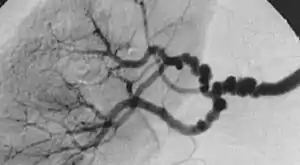

| The "string-of-beads" feature in multi-focal fibromuscular dysplasia. The sign is caused by areas of relative stenoses alternating with small aneurysms. | |

The second type, multi-focal fibroplasia, involves thickening of the media and collagen formation. It is typically reported as having the appearance of a ‘string of beads’ on angiographic review.[4] "The 'bead' component is often larger than the normal arterial lumen, and in a subset of patients with FMD, aneurysms are present that may require treatment."[4] The multi-focal subtype of FMD accounts for nearly 80% to 90% of all FMD cases.[4] (previously known as medial)